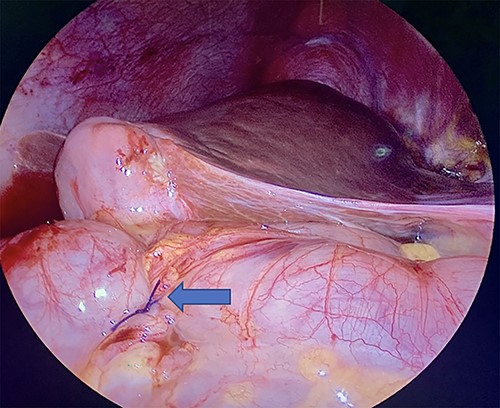

Diagnostic laparoscopy of the abdomen was performed demonstrating diffuse carcinomatosis secondary to known primary gallbladder carcinoma. A portion of the ascending colon was adherent to the abdominal wall and was carefully dissected off. There was no full thickness erosion of the stent, and the stent was palpated through the colon at the ascending colon using bowel graspers. Colonoscopy was next performed, identifying the stent lodged in the mid-ascending colon and another intraluminal portion of the proximal transverse colon that appeared abnormal (Fig. 2A and B). The stent was successfully removed with rat tooth forceps by gastroenterology. The colorectal surgery team then performed two serosal suture repairs on the ascending and transverse colon (Fig. 3).

(A) Ascending colon demonstrating ulceration and the biliary stent lodged within colonic wall. (B) Stent across transverse colon with punctate erythema.